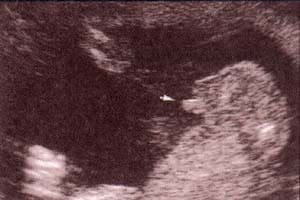

Diagnóstico Prenatal -  34 semanas. Diagnóstico Prenatal -  38 semanas. al final del tercer trimestre

fig. 51.– (c). 34 semanas. fig. 51.– (d). 38 semanas. al final del tercer trimestre es frecuente observar líquido en el escroto en escasa a moderada cantidad que corresponde al hidrocele fisiológico.